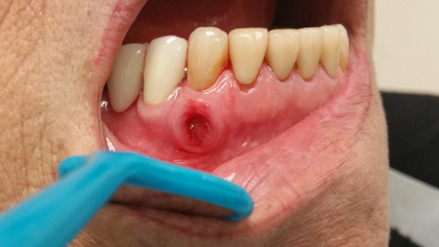

• дефекты слизистых оболочек с гладкими или неровными краями с оголением кости на верхней или нижней челюсти, сохраняющиеся более восьми недель.

• низкоинтенсивная лазеротерания на область поражения: значительное уменьшение болевого синдрома, размеров очага поражения, отека, размеров и количества свищевых ходов и объема гнойного отделяемого у пациентов с остеонекрозом нижней челюсти на фоне введения.

При выборе хирургического метода, производят кюретаж лунок удаленных зубов, резекцию челюсти, секвестрэктомию.